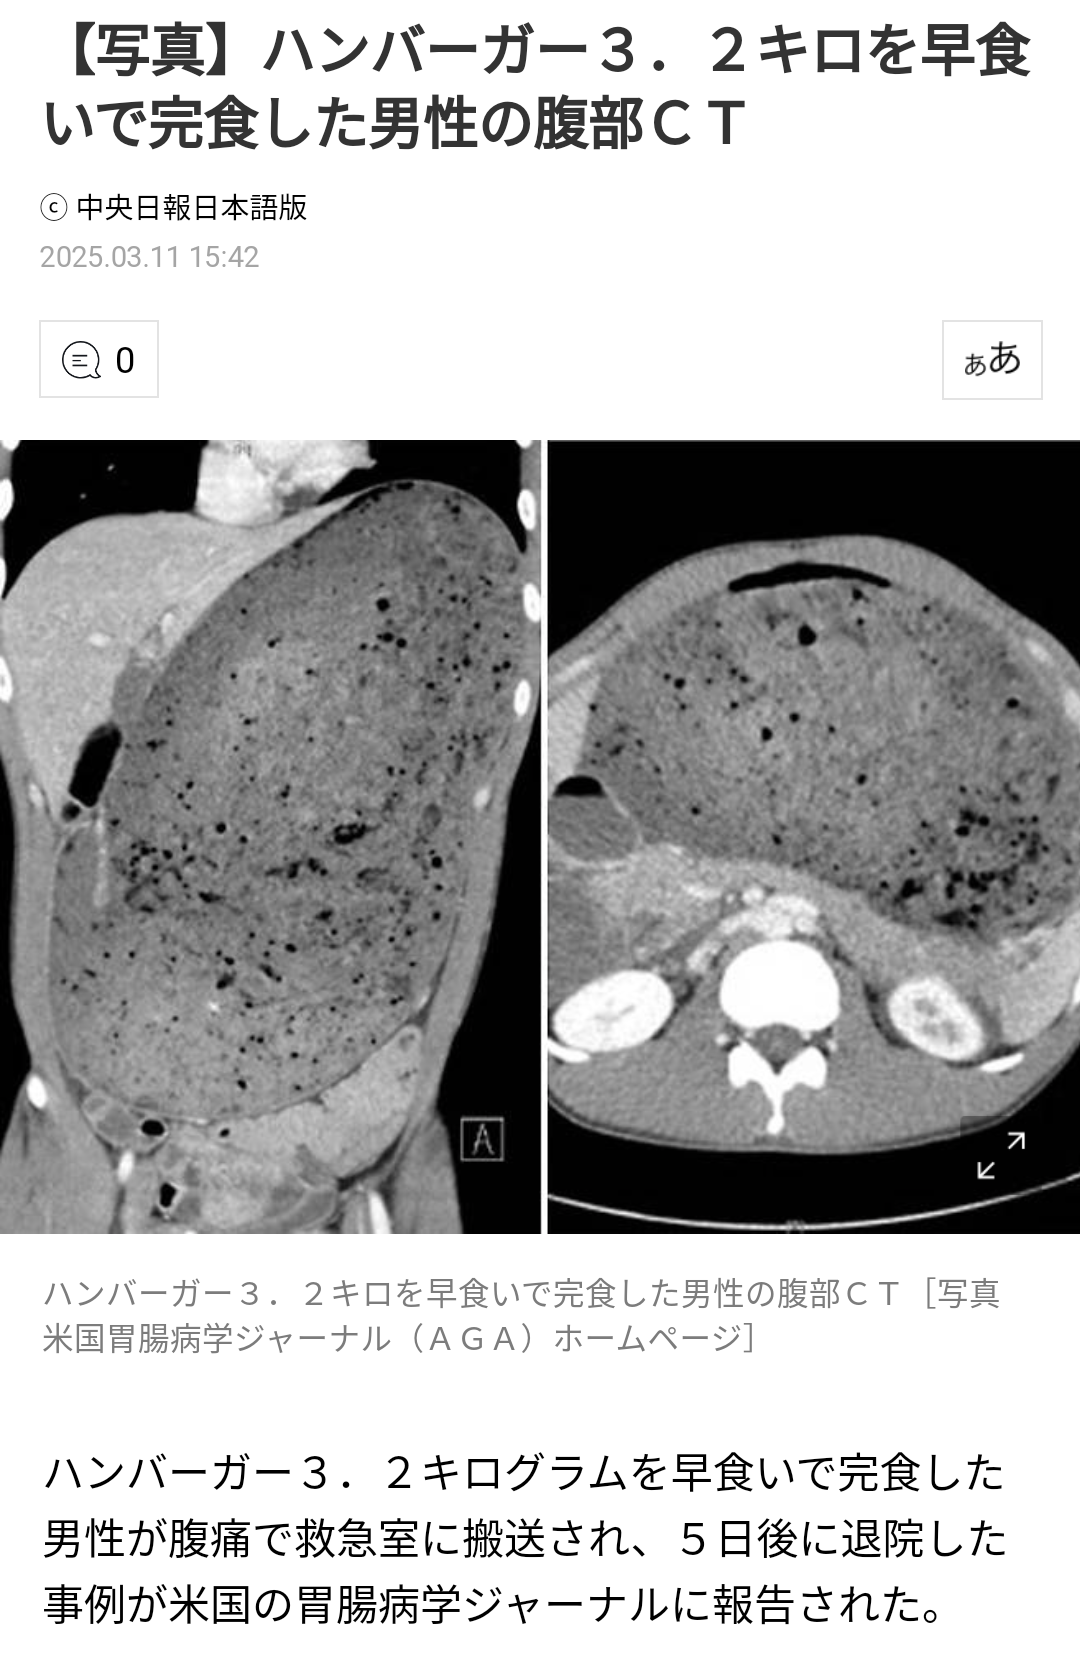

ヤフーニュースA氏はこの大会で3.2キログラムに及ぶハンバーガーを30分で完食した。8時間後、男性のお腹が膨らみ始め、嘔吐とともに腹痛を訴え、救急室に運ばれた。

病院で腹部のCT撮影をした結果、A氏の胃と十二指腸は摂取した食べ物によって巨大に伸びていた。未消化の食べ物が周辺の臓器を圧迫し、膵臓がつぶれていた。また、血液中の総白血球数と血清クレアチニン、血清アミラーゼの数値も深刻に高かった。